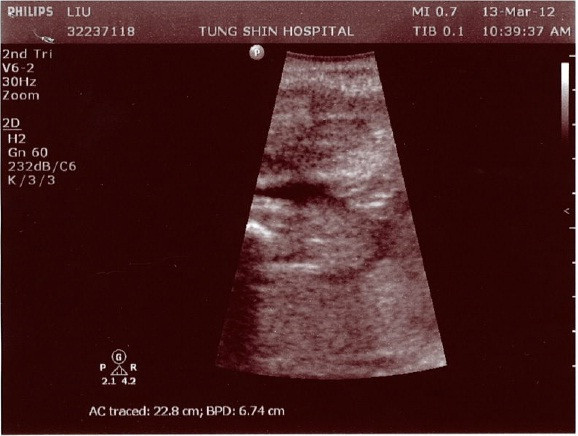

10點,但是大約到10:30才輪到我們看到醫生。醫生是個有點年紀的華人,說中文就可通,看著我準備的先前產檢資料,對於各項結果非常滿意。也做了超音波,醫生邊看超音波邊說:「很愛動啊,一直動啊」,看來招財也和招弟一樣都被歸為hyper型的孩子。醫生推估招財目前為1公斤,且說以後每次產檢都要照超音波要追蹤孩子的生長情況。我和鍵哥一致認為這是因為每照超音波他都可以收錢,所以照得樂此不疲。

這是啥? 不會是跟我再再再次的確認招財是女生吧?!

這花溝溝的又是啥? 如果以後每次都給我這種不清不楚又不曉得是哪裡的照片, 我就跟你拼了!!